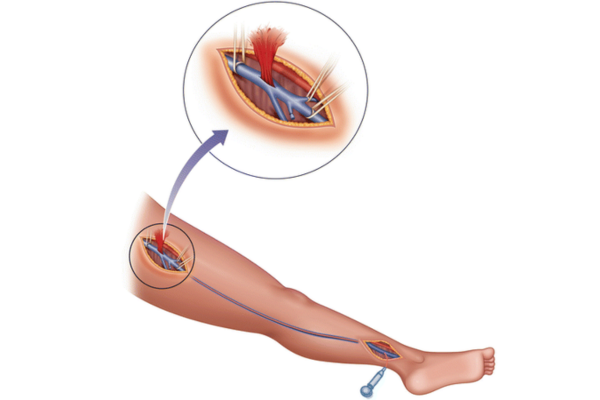

Mechanical thrombectomy is an emergency procedure for strokes caused by blocked brain arteries. It is performed when sudden weakness, speech difficulty, or paralysis occurs.

Special catheters remove the clot quickly, restoring blood flow, minimizing brain damage, and significantly improving recovery when done within the treatment window.